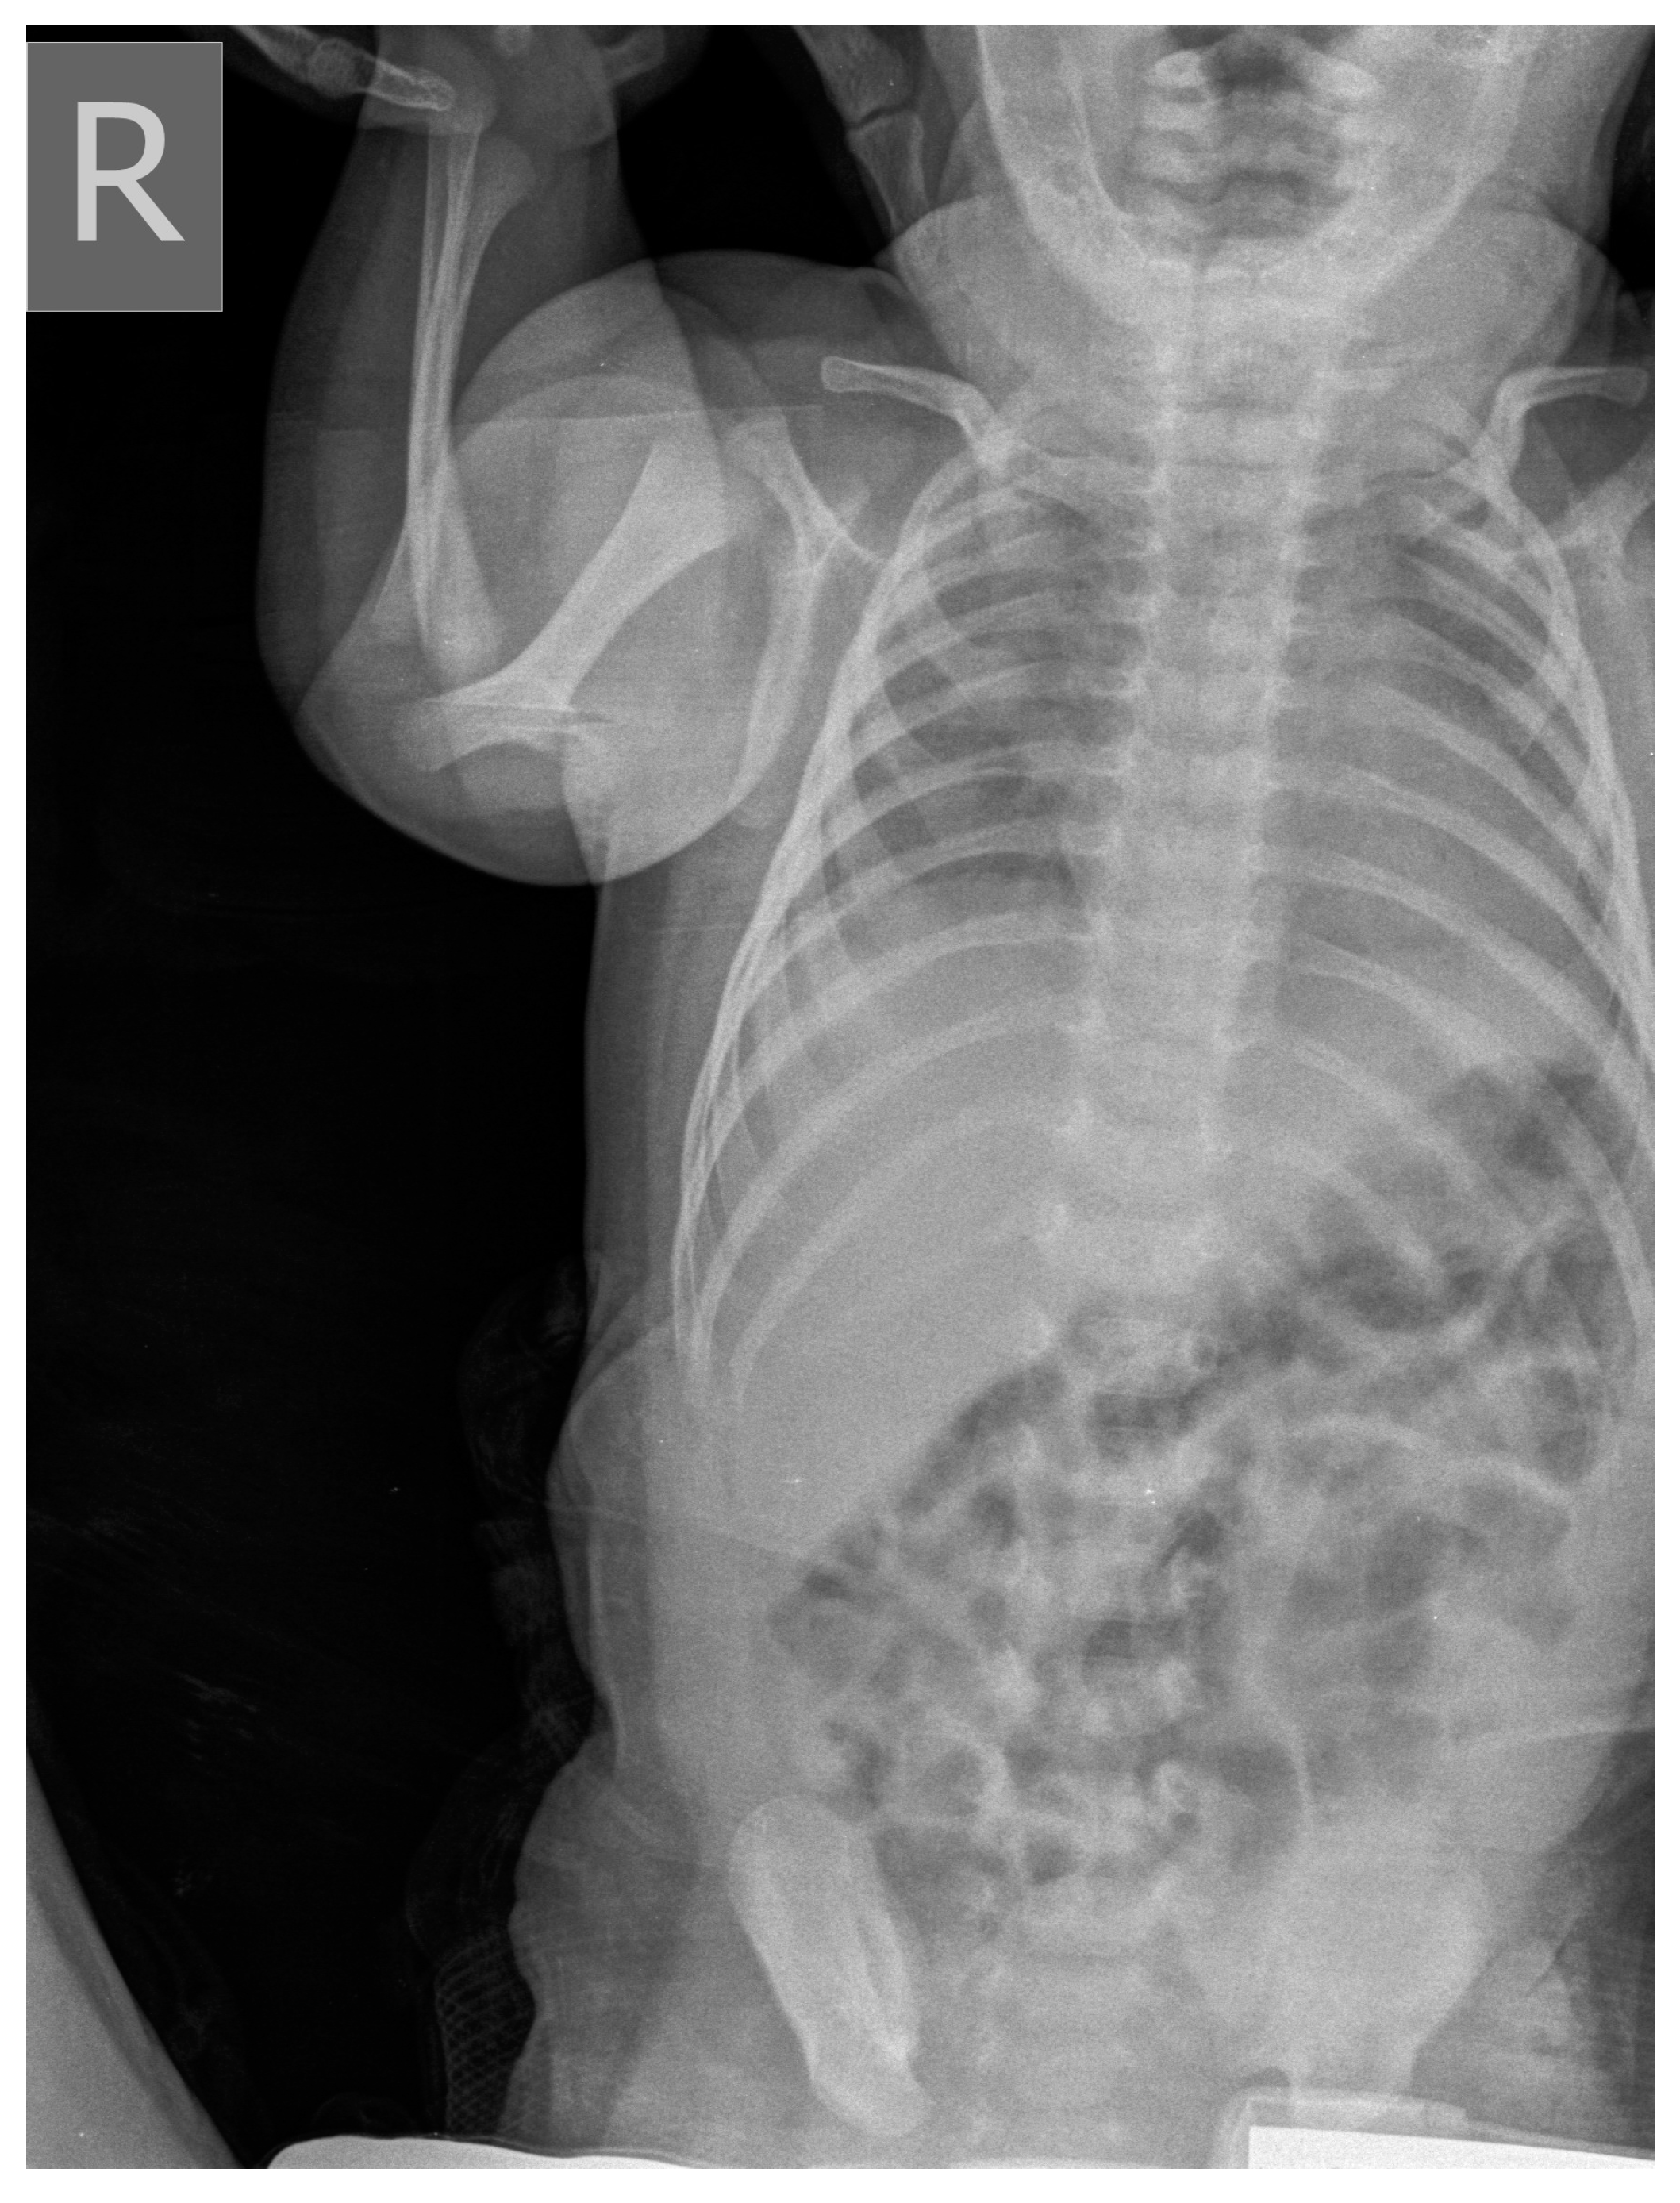

| Clinical picture at admission in Pediatric Clinic UCC | NN1 had a preserved sensorium, was high febrile 39.4 °C (rectal), with tachy-dyspnea, sobs, and moans, indents jugulum, dissatisfied cries, TM 4050 g, subclinical jaundice of the skin, and visible mucosa. Auscultation revealed attenuated respiratory sound, diffusely fine crackles, SaO2 82%, R 56/min, F 196/min. The umbilical stump persisted, the surrounding skin became red and swollen, there was hypotonia of the body axis, large fontanelle within the bony borders, greatness 20 × 30 mm. The other physical findings were normal. | NN2 had the preserved sensorium, was afebrile 37.7 °C (rectal), TM 3920 g, eupnoeic, presented sobs and moans, plethoric and icteric skin, nasal vestibules filled with seromucous secretion, and hyperemic throat. Auscultatory revealed a normal breathing sound is heard with transmitted wheezes from the upper parts of the airways and systolic murmur of 1-2/6 according to Levin, SaO2 97%, R 32/min, F 168/min. The umbilical stump persisted, thin, and the borders developed a serous–hemorrhagic discharge. There was mild hypotonia of the shoulder girdle and trunk axis, primitive reflexes were slowly elicited, large fontanelle was below the plane of the bony borders, and slightly spaced sutures, greatness 40 × 40 mm. The other physical findings were normal. |

| Tracheal aspirate by RT-PCR testing | Legionella pneumophila serogroup 2-15 | Legionella pneumophila serogroup 2-15 | |

| Culture of tracheal aspirate on the GVPC nutrient media | Legionella pneumophila, Pseudomanas aeriginosa | Legionella pneumophila | |